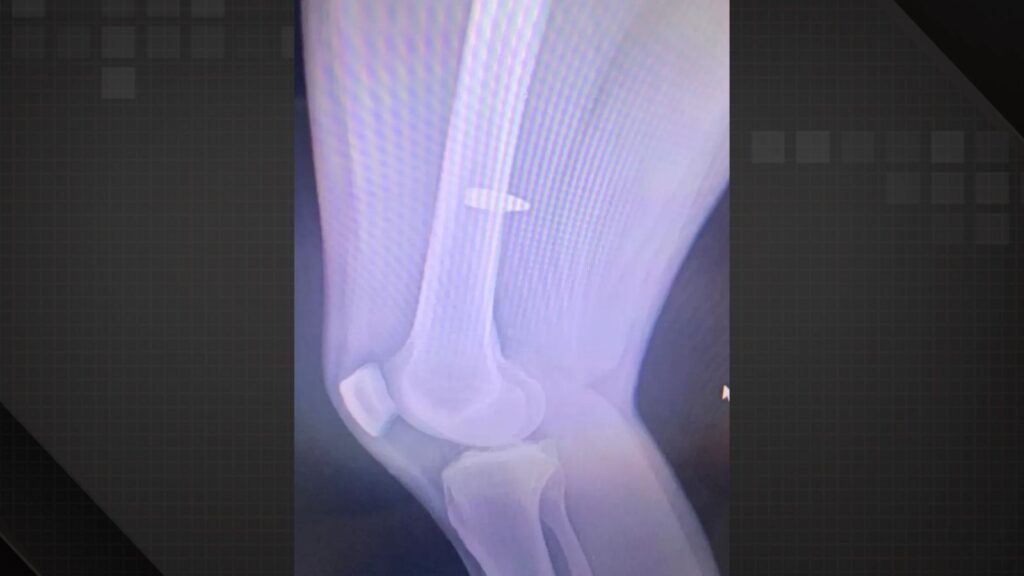

“Foi um único barulho (de tiro). A gente escutou um estalo muito próximo da gente, tipo assim, como se fosse um estalo dentro da quadra mesmo. Aí eu já senti a dor no joelho. Depois, vendo o raio X, a bala entrou bem perto do meu joelho e subiu. Então, esse barulho que a gente escutou foi ela batendo no chão e ricocheteando para cima” – contou o jovem.

Foto: Raio-x de Pedro “Tubarão” – Foto: Arquivo pessoal